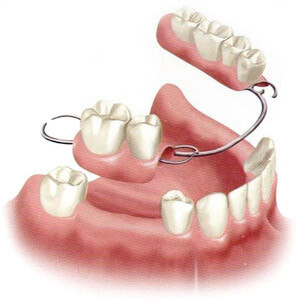

Removable partial dentures use plastic teeth to replace missing teeth. These plastic teeth are fixed on an acrylic plate and clasps are placed in the plate to take support from adjacent teeth.